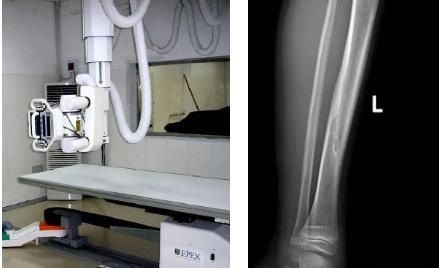

一般骨科創(chuàng)傷的病人,只要到影像科拍一張X光片,很快就會(huì)明確診斷有沒(méi)有骨折。然而有一些特殊類型骨折的病人,由于拍片影像重疊的緣故,或者骨折未發(fā)生明顯移位,病變可能顯示不出來(lái),等過(guò)了一段時(shí)間后,骨折部位才能夠顯示清楚。這種類型的骨折,叫做隱匿性骨折。若在臨床上診斷及時(shí)且明確,及時(shí)固定患者的骨折部位,進(jìn)行適當(dāng)治療并減少運(yùn)動(dòng),對(duì)患者的恢復(fù)有重要意義。

1.定期復(fù)查。一般于骨折后2-4周,骨折進(jìn)入骨痂期,骨折斷端有新生骨形成,呈明顯高密度,無(wú)論是X線或是CT,都能比較清晰觀察到,通過(guò)前后圖像對(duì)比,較容易診斷隱匿性骨折。